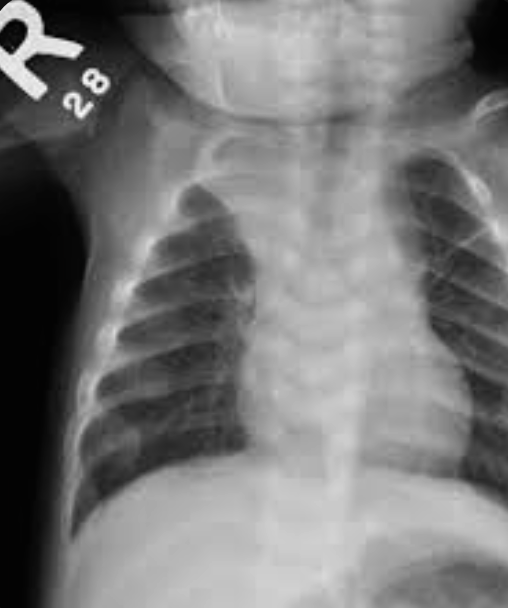

Case: Infant with Poor Weight Gain

- 9-month-old infant with poor weight gain, recurrent chest infection, and cardiac murmur

- Write 2 abnormalities in the X-ray

- Differential diagnosis

- More likely right-left shunt, boot-shaped heart

- TOF if cyanosis